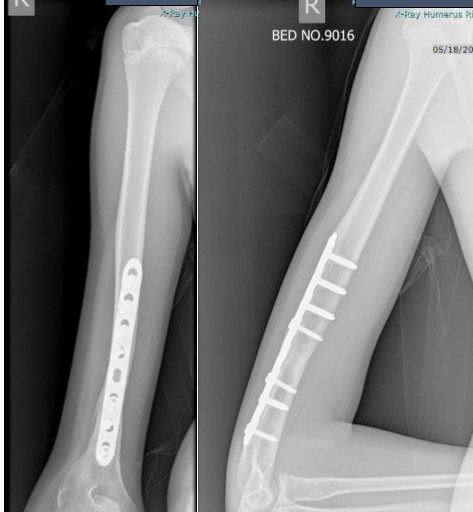

By 3 months, early signs of healing were visible. Therapy was continued, and by 6 months the radiographs showed complete union (Fig. 5).

The patient had regained a full range of motion at the elbow and shoulder. He subsequently underwent implant removal and returned to pain-free, unrestricted activities (Fig. 6).

Figure 6: Radiograph at 6 months after low-intensity pulsed ultrasound showing complete union.